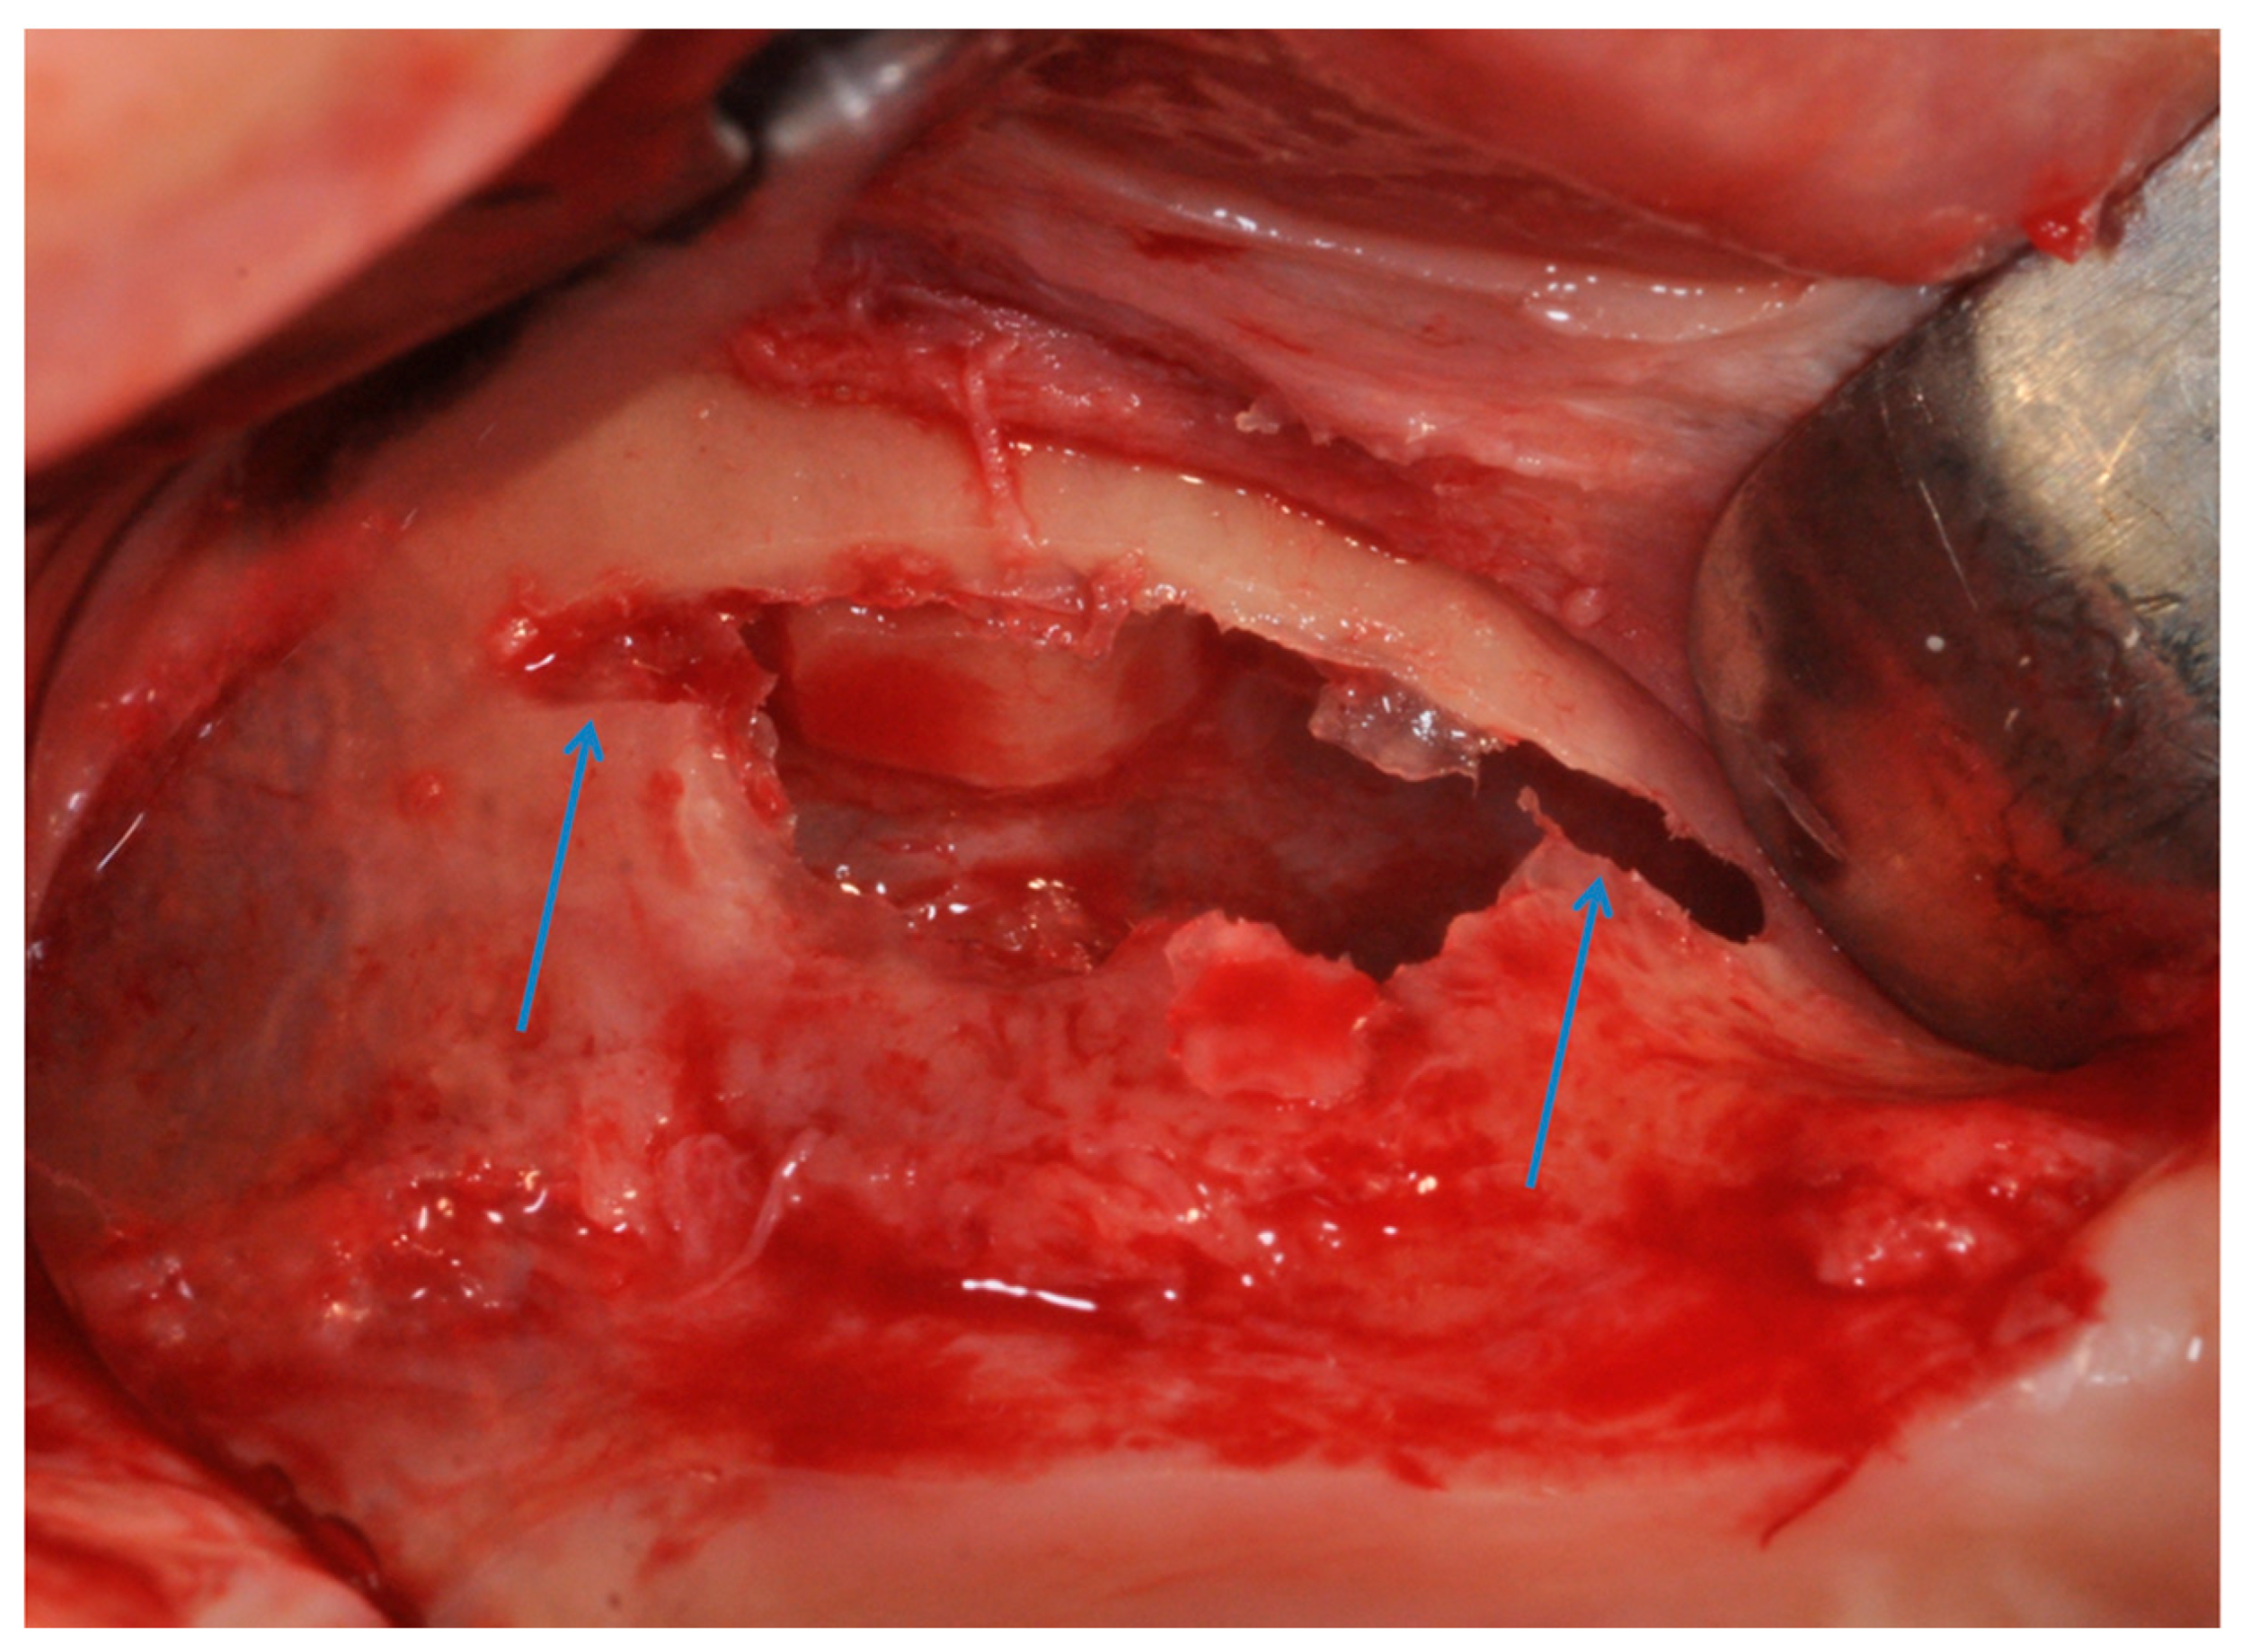

4. Materials and Methods